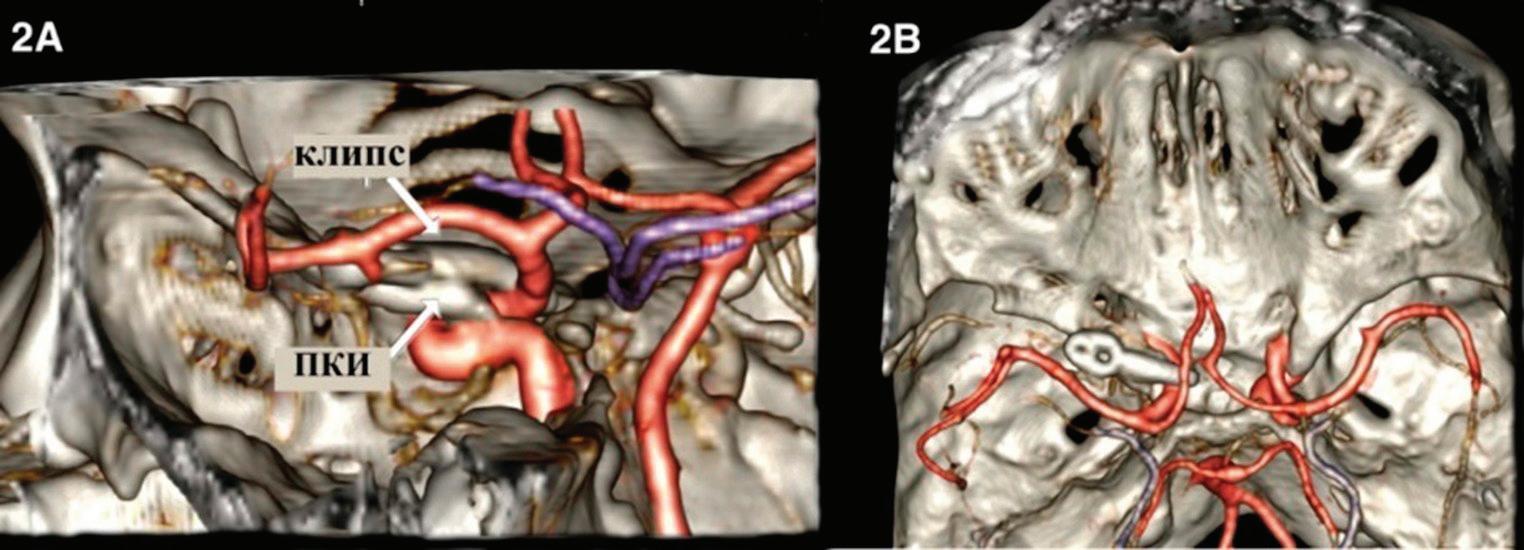

ПРЕДНА КЛИНОИДЕКТОМИЯ В. Наков

74 РЯДЪК